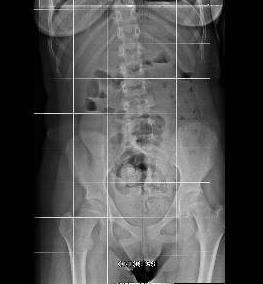

´In general anesthesia, patient prone, neurophysiological monitoring (EMG-triggered stimulation parameters: THR 0.2 ms, 1 Hz; TETANIC 0.1 ms, 50 Hz for 1 sec. Recording muscles: adductor longus, vastus lateralis, tibialis anterior, peroneus longus, gastrocnemius, abductor hallucis, anal sphincter bilaterally, iliopsoas). Midline skin incision from L1 to L3, median fascia incision, skeletonization of L2 lamina and partial of L1 and L3; L2 laminotomy; median dural incision and suspension; opening of the arachnoid; identification of midline (filum terminale and conus medullaris); rhizotomy performed as follows:

TOTAL section: left 50.6%; right 56.8%.

Hemostasis, watertight dural suture (verified with Valsalva maneuver), replacement of L2 lamina fixed with silk-0; muscular, fascial, subcutaneous and skin closure.ª